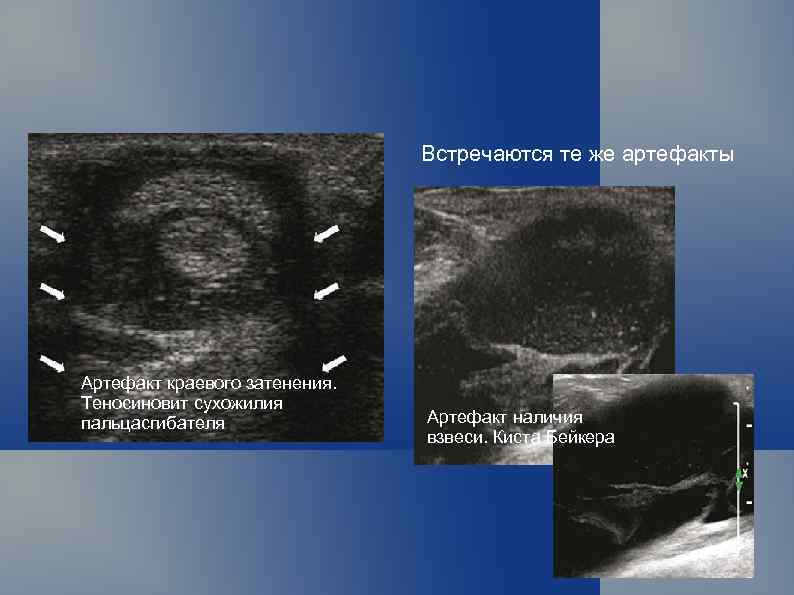

Встречаются те же артефакты Артефакт краевого затенения. Теносиновит сухожилия пальцасгибателя Артефакт наличия взвеси. Киста Бейкера